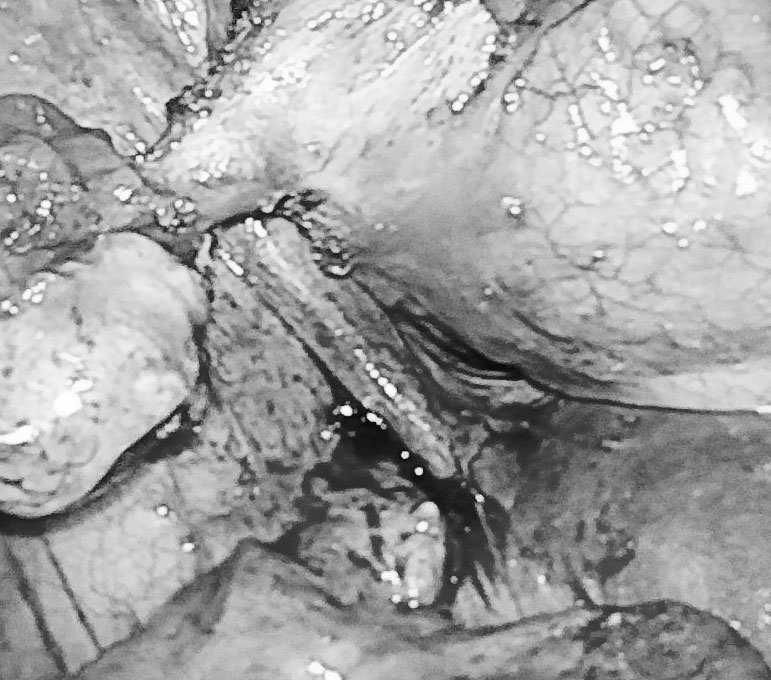

Trong quá trình phẫu thuật, các bác sĩ tìm thấy khối u kích thước 3x3 cm. Xẻ khối u, ê-kíp thấy tổ chức tóc, xương, dịch bã đậu, mỡ bên trong. Khối u quái của nữ bệnh nhân được phẫu tích và đưa ra khỏi ổ bụng sau 90 phút phẫu thuật.

Nữ bệnh nhân đã được lấy khối u quái ra khỏi ổ bụng